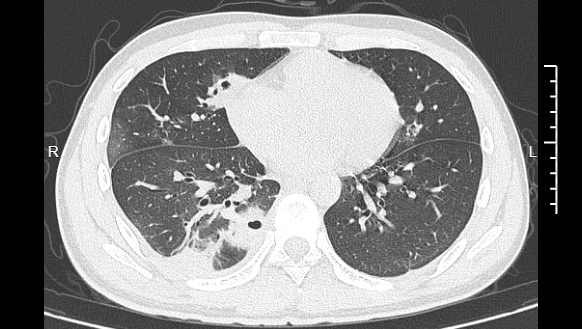

熬到第三天,小林已经烧到39℃,赶紧去医院就诊。接诊的主任医师丁群力一看他的症状,立刻安排了CT检查。结果显示:小林的肺里有十几个空洞,部分肺组织已经坏死,这是典型的血源性肺脓肿。

▲小林的CT影像显示肺里有多个空洞